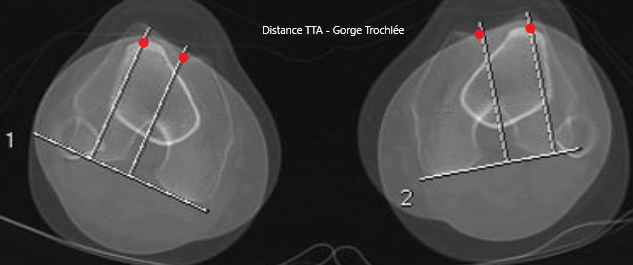

TA-GT

C + E (condyles + TTA)

C

Condyles (Arche romaine)

E

TTA